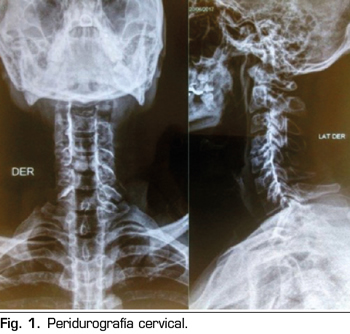

Figura 1